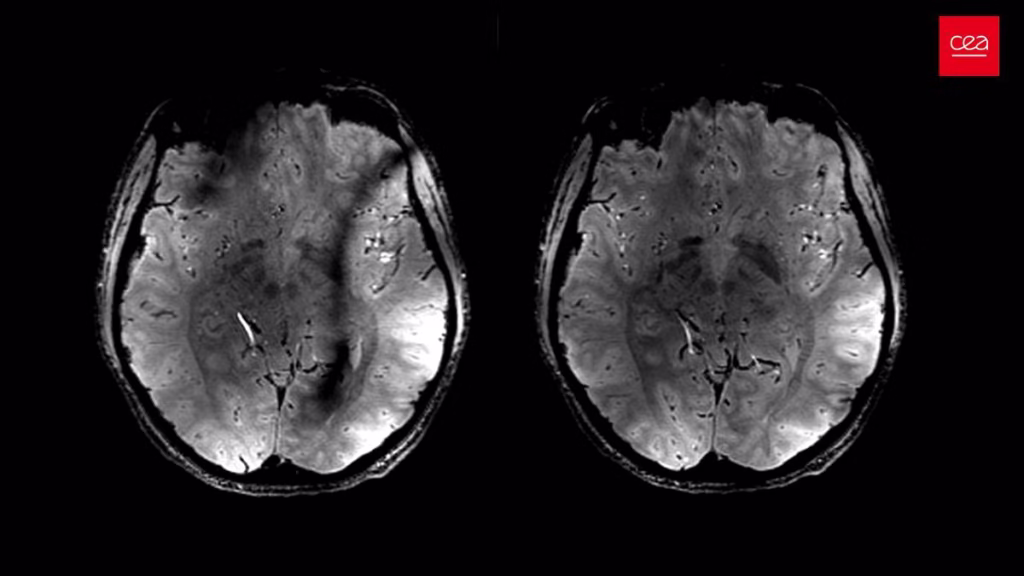

Um único exame de ressonância magnética pode ser capaz de indicar a velocidade do envelhecimento cerebral. É o que aponta um estudo feito por neurocientistas da Universidade Duke, nos Estados Unidos, publicado em julho na revista Nature Aging.

A partir da análise de 50 mil exames de imagem, a pesquisa revela que a espessura do córtex cerebral (a camada mais externa do órgão) e o volume da massa cinzenta estão entre os marcadores mais relevantes para avaliar a saúde do cérebro. Esses padrões estruturais podem ser indicativos de questões como perda de memória e risco de morte a partir de sinais sutis de atrofia cerebral.

O modelo não depende de novas tecnologias além da análise feita por inteligências artificiais dos exames de imagem já disponíveis. A proposta apenas estabelece parâmetros que interpretam a estrutura cerebral captada por ressonâncias convencionais. Segundo os autores, tal análise se mostrou mais precisa para avaliar o envelhecimento biológico do que marcadores baseados em exames de sangue e de desempenho físico.